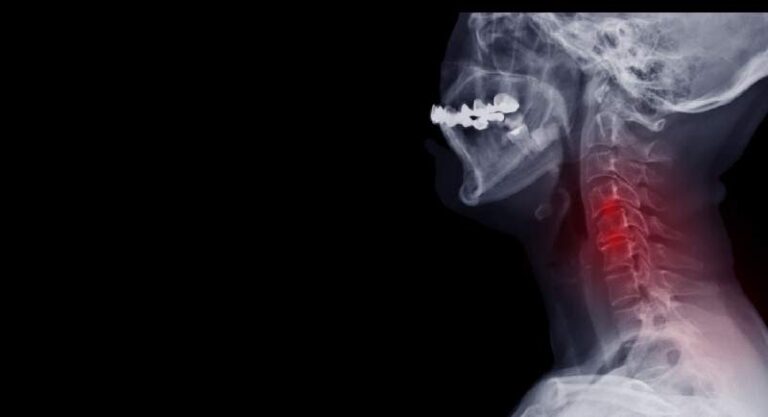

Stenoza szyjną